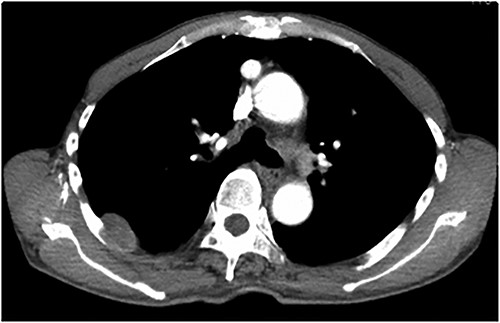

An asymptomatic 79-year-old male who was diagnosed with a chest wall tumor, which had been detected by an X-ray of a health examination, presented to our hospital for surgical intervention. He had no relevant past medical history, including malignant neoplasm or radiation therapy. No mass was palpable. The chest X-ray revealed a tumor shadow of 3 cm in diameter in the right upper lung field (Fig. 1). Chest contrast computed tomography (CT) revealed a well-circumscribed tumor shadow measuring 37 × 27 mm in the posterolateral region of the right sixth intercostal space, the size of which had increased 1.5 times in the previous 3 months (Fig. 2). Thoracic magnetic resonance imaging (MRI) revealed a solid tumor that was enhanced by gadolinium on T1-weighted imaging (T1WI). T2-weighted imaging (T2WI) showed a homogeneous mass with iso-intensity. The tumor was inhomogeneous while demonstrating a maximum standardized uptake value (SUV) of the [18F]-2-deoxy-D-glucose (FDG) uptake under positron emission tomography (PET), with a range of 3.4–4.1 (Fig. 3). There was no significant uptake at other sites, including the mediastinal lymph nodes. No tumor-markers (CEA, proGRP and CYFRA) were detected in a laboratory analysis. Based on these examinations, we suspected a neurogenic tumor, especially schwannoma, and we opted for surgical resection. Considering the fact that ~10% of neurogenic tumors are malignant and the FDG uptake was heterogeneous, we planned to perform an intraoperative frozen section examination. We first performed tumor resection. The operation was performed in the left lateral position under general anesthesia. A 30° viewing angle thoracoscope was set at the middle axillary line of the seventh intercostal space. The tumor was smooth, slightly solid and covered with pleura (Fig. 4). We added a 4-cm incision just above the tumor, while verifying its location through the thoracoscope, and easily removed it from the chest wall. The tumor was diagnosed as sarcoma based on the frozen section examination. Therefore, we added removal of a portion of the sixth and seventh right rib. We excised the chest wall with a 2-cm margin from the lesion, confirming an adequate length through the thoracoscope. Chest wall reconstruction was performed with DUALMESH® (Gore, Flagstaff, AZ). On the cut section, the tumor appeared as solid, smooth-surfaced and encapsulated whitish mass of 3.7 × 2.7 cm in size. Upon microscopic examination, the tumor was composed of fascicles of highly atypical spindle cells mitotic figures exceeding 15 per 10 high-power fields. Immunohistochemistry was positive for αSMA (Fig. 5), desmin and caldesmon and was negative for S-100 protein (data not shown). All margins were negative, and no invasion to the peripheral organs was seen. We concluded that the tumor was leiomyosarcoma of the chest wall. He was discharged on post-operative day 10 without any complications. Since we considered that curative resection had been achieved, no adjuvant therapy was performed. He is still being followed up; however, liver and multiple lung metastases were detected at 5 years after surgery.

On CT, thoracic leiomyosarcomas are usually characterized by huge soft tissue masses with heterogeneous enhancement because of bleeding, necrosis and other heterogeneous textures. Larger tumors can also push against the surrounding organs and can occasionally be invasive [6)]. Leiomyosarcomas show enhancement on MRI, while they also show a high FDG uptake on PET-CT [7]. Alternatively, schwannoma shows a smooth tumor with homogeneous enhancement on CT. Schwannomas may be heterogeneous due to necrosis or hemorrhage within the mass. On MRI, the tumor is iso- to hypo-intense, while it is also enhanced with contrast media on T1WI and is iso- to hyper-intense on T2WI [8]. The administration of gadolinium causes homogeneous enhancement [9]. In this case, homogeneous enhancement with gadolinium and a clear border were similar to the characteristics of schwannoma. The heterogeneous FDG uptake on PET-CT and rapid growth of tumor were the only findings that raised the suspicion of malignancy.